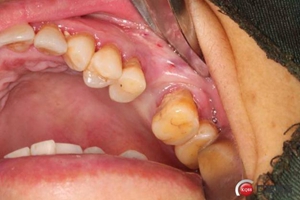

改良式外提升工具盒-外提 科貿(mào)嘉友收錄

大家好,我是梁老師的助理小依。由于梁老師每天手術(shù)檔期安排較滿,加上經(jīng)常出差講課,沒(méi)有時(shí)間整理病例 。為了方便大家更及時(shí)的了解梁老師最新手術(shù)動(dòng)態(tài),以后將由我為大家整理并推送梁老師最新經(jīng)典案例。案例文字旁白少,但圖片會(huì)盡量完整展示手術(shù)全過(guò)程,供大家學(xué)習(xí)參考。有任何問(wèn)題,可以留言,梁老師會(huì)親自為大家解答。感謝大家對(duì)梁老師的支持和關(guān)注!